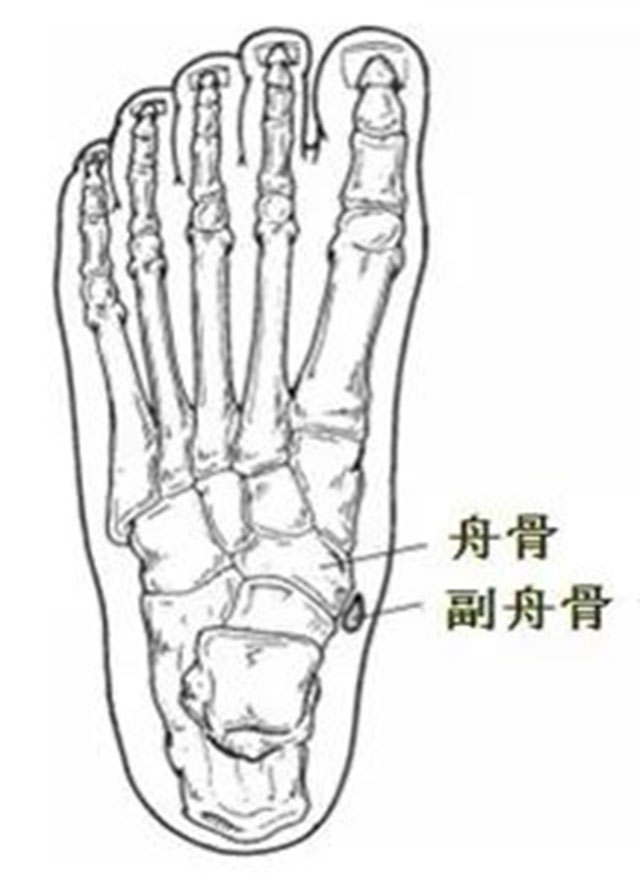

什么是副舟骨?

副舟骨被称为多余的骨头。副舟骨位于舟骨内后侧,属于先天性发育异常,是幼年时期的副舟骨骨化中心未能与舟骨结节完全融合,使得舟骨旁边多出一块骨头,这就是副舟骨。